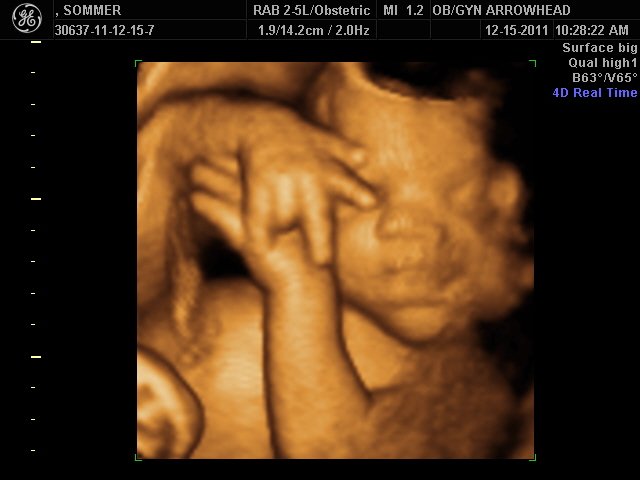

We offer complimentary 3D/4D Ultrasounds to all our OB patients around 30 weeks! The following photos are some examples of our work, shown with permission from our patients.